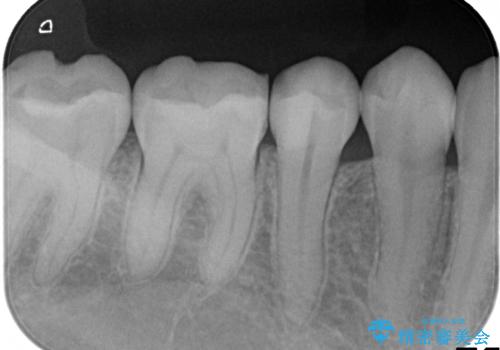

虫歯が大きく広がっていましたが、顕微鏡を使って慎重に治療を行うことで、神経をとってしまうことなく治療することができます。